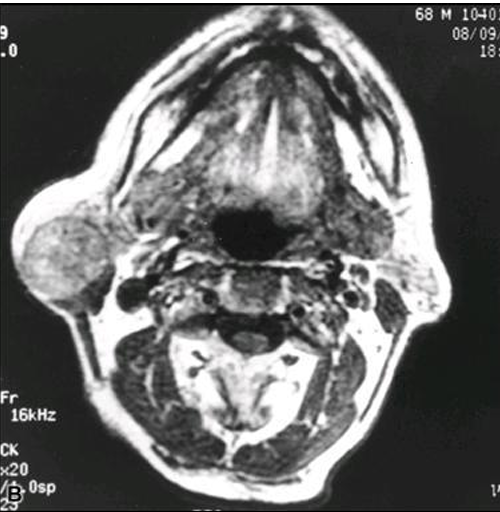

طبقي محوري لورم مختلط بالنكفة

يشكل المرنان الوسيلة الأكثر حساسية في تحديد امتداد الورم للنسج الرخوة وإصابة البنى المجاورة . ويمكن الاستعانة بإجراء الرشافة بالإبرة الرفيعة في بعض الحالات .